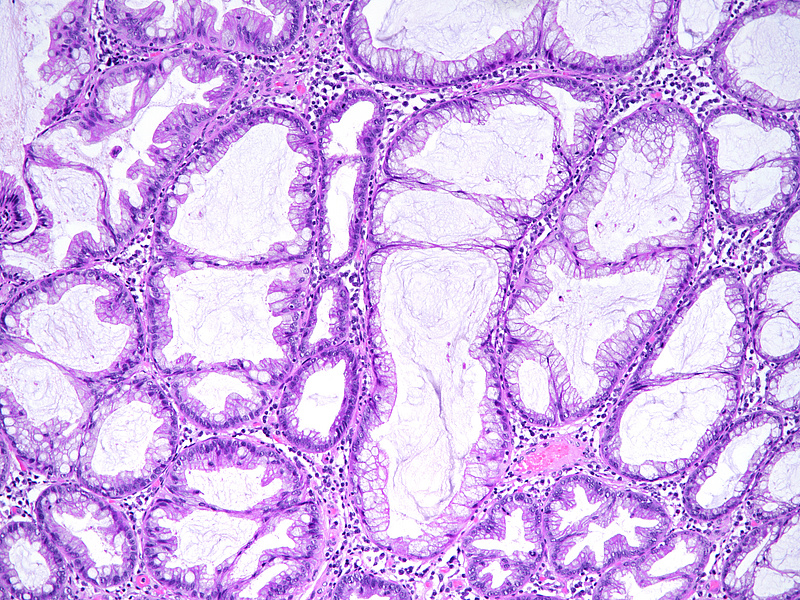

The ascending colon polyp is a serrated polyp characterized by a combination of two morphological patterns which are sessile serrated lesion (SSL) and traditional serrated adenoma (TSA). The former is formed by architecturally distorted serrated crypts with deep serrations, basal crypt dilatation and lateral growth along the muscularis mucosae (Panels A-B). Some foci of stromal proliferation resembling perineural cells are also seen within this component (Panel C). The TSA component has typical slit-like serrations, lined by tall columnar cells with intensely eosinophilic cytoplasm and pencillate nuclei (Panels D-E). Abrupt transition to dysplastic mucosa and glands are present, where the glands display more complex and crowded architecture with little intervening lamina propria (Panel F). The dysplastic cells show features of adenomatous dysplasia characterized by columnar cells with enlarged hyperchromatic nuclei, pseudostratification and reduced goblet cells (Panel G). In some areas, the cells display high grade cytology with more rounded nuclei and loss of polarity. MLH1 immunostaining was preserved in both the non-dysplastic and dysplastic glands with higher intense staining seen in the latter (Panel H).